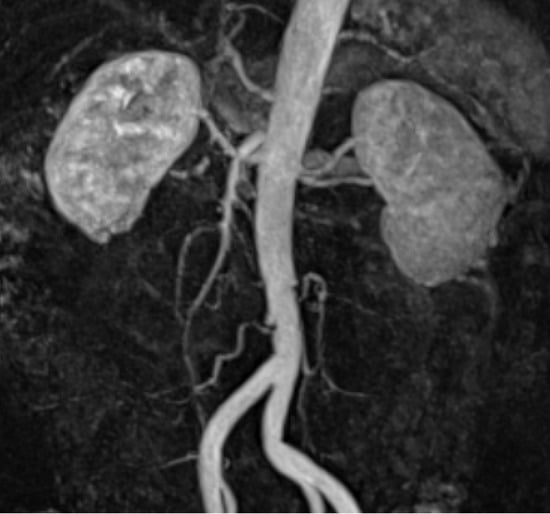

Asymptomatic Idiopathic Renal Infarction Detected Incidentally on Contrast-Enhanced Computed Tomography: A Case Report

2. Case Presentation